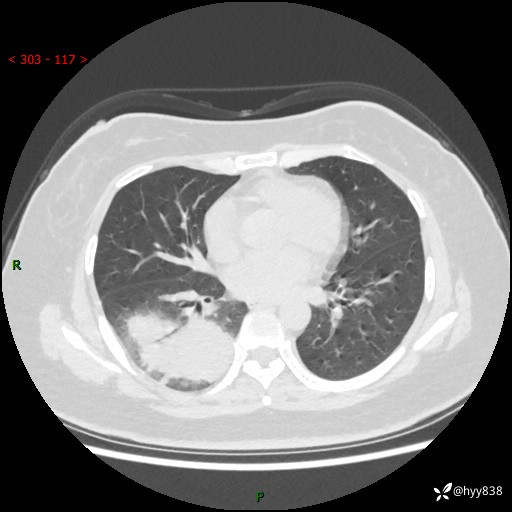

大叶性肺炎的表现形式,晒晒鉴别诊断吧…结果公布~

简要病史:患者8天前无明显诱因出现咳嗽、咳痰,为绿色脓痰,无明显加重与缓解因素,无高热、寒战,无呼吸困难,无大量脓痰,无哮鸣音,于当地医院行胸片示右下肺团块影,性质待定,予口服药物治疗症状未见明显改善,具体药名不详,为求进一步诊治来我院就诊,门诊以“肺占位性病变”收入我科进一步诊治。 患者自发病以来,精神、饮食尚可,睡眠欠佳,大小便正常,体力、体重未见明显异常。

辅助检查:CT

胸部CT平扫

增强动脉期+静脉期